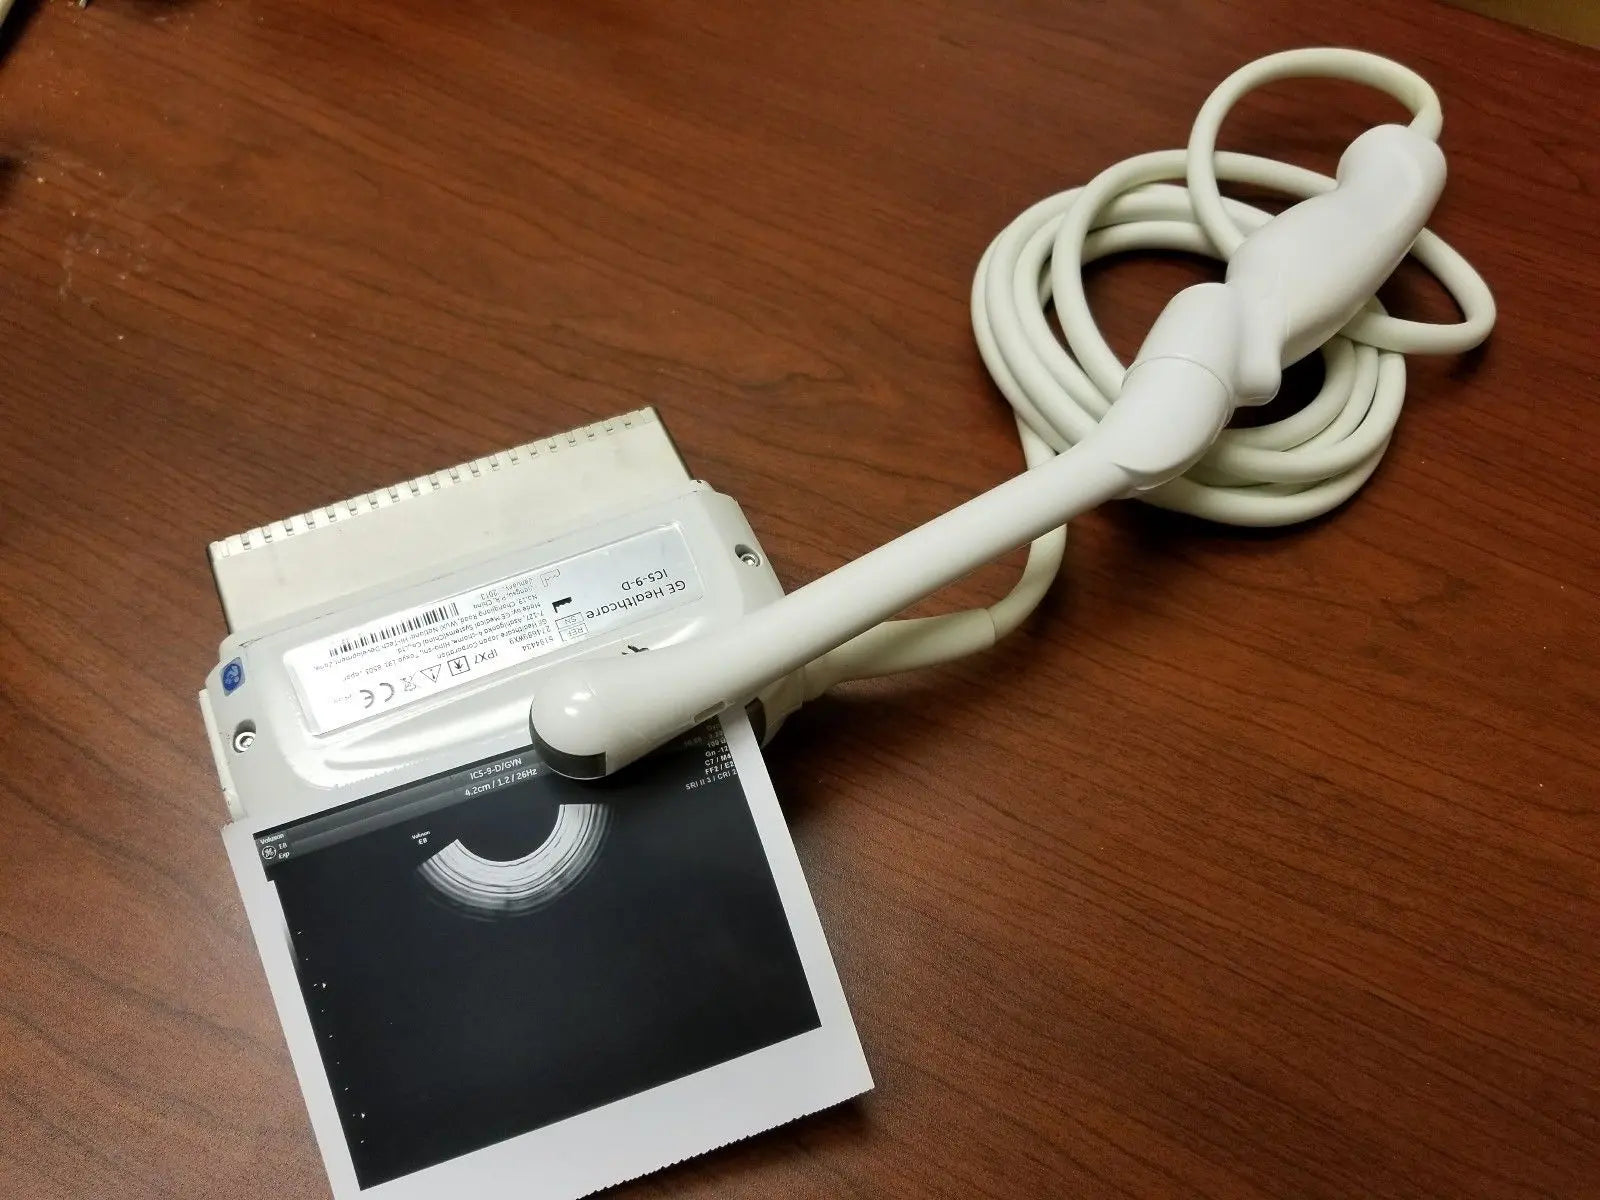

2017 GE IC9 -RS probe for GE Ultrasound

Sale price$ 8,395.14